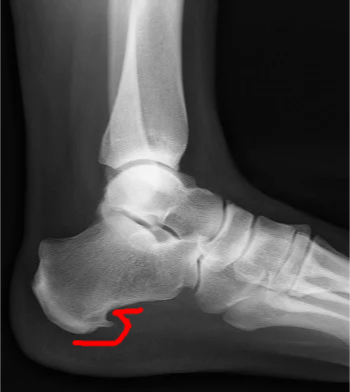

Radiology - Hallux Valgus

- XR views:

- AP standing:

- Lateral deviation of big toe

- Increased varus of 1st MT

- Subluxation of MT-Phal. joint

- “Calcaneal Spur” on XR:

- It’s a result NOT the cause

- Implies chronicity

- Not diagnostic

- Present in 10% of normal